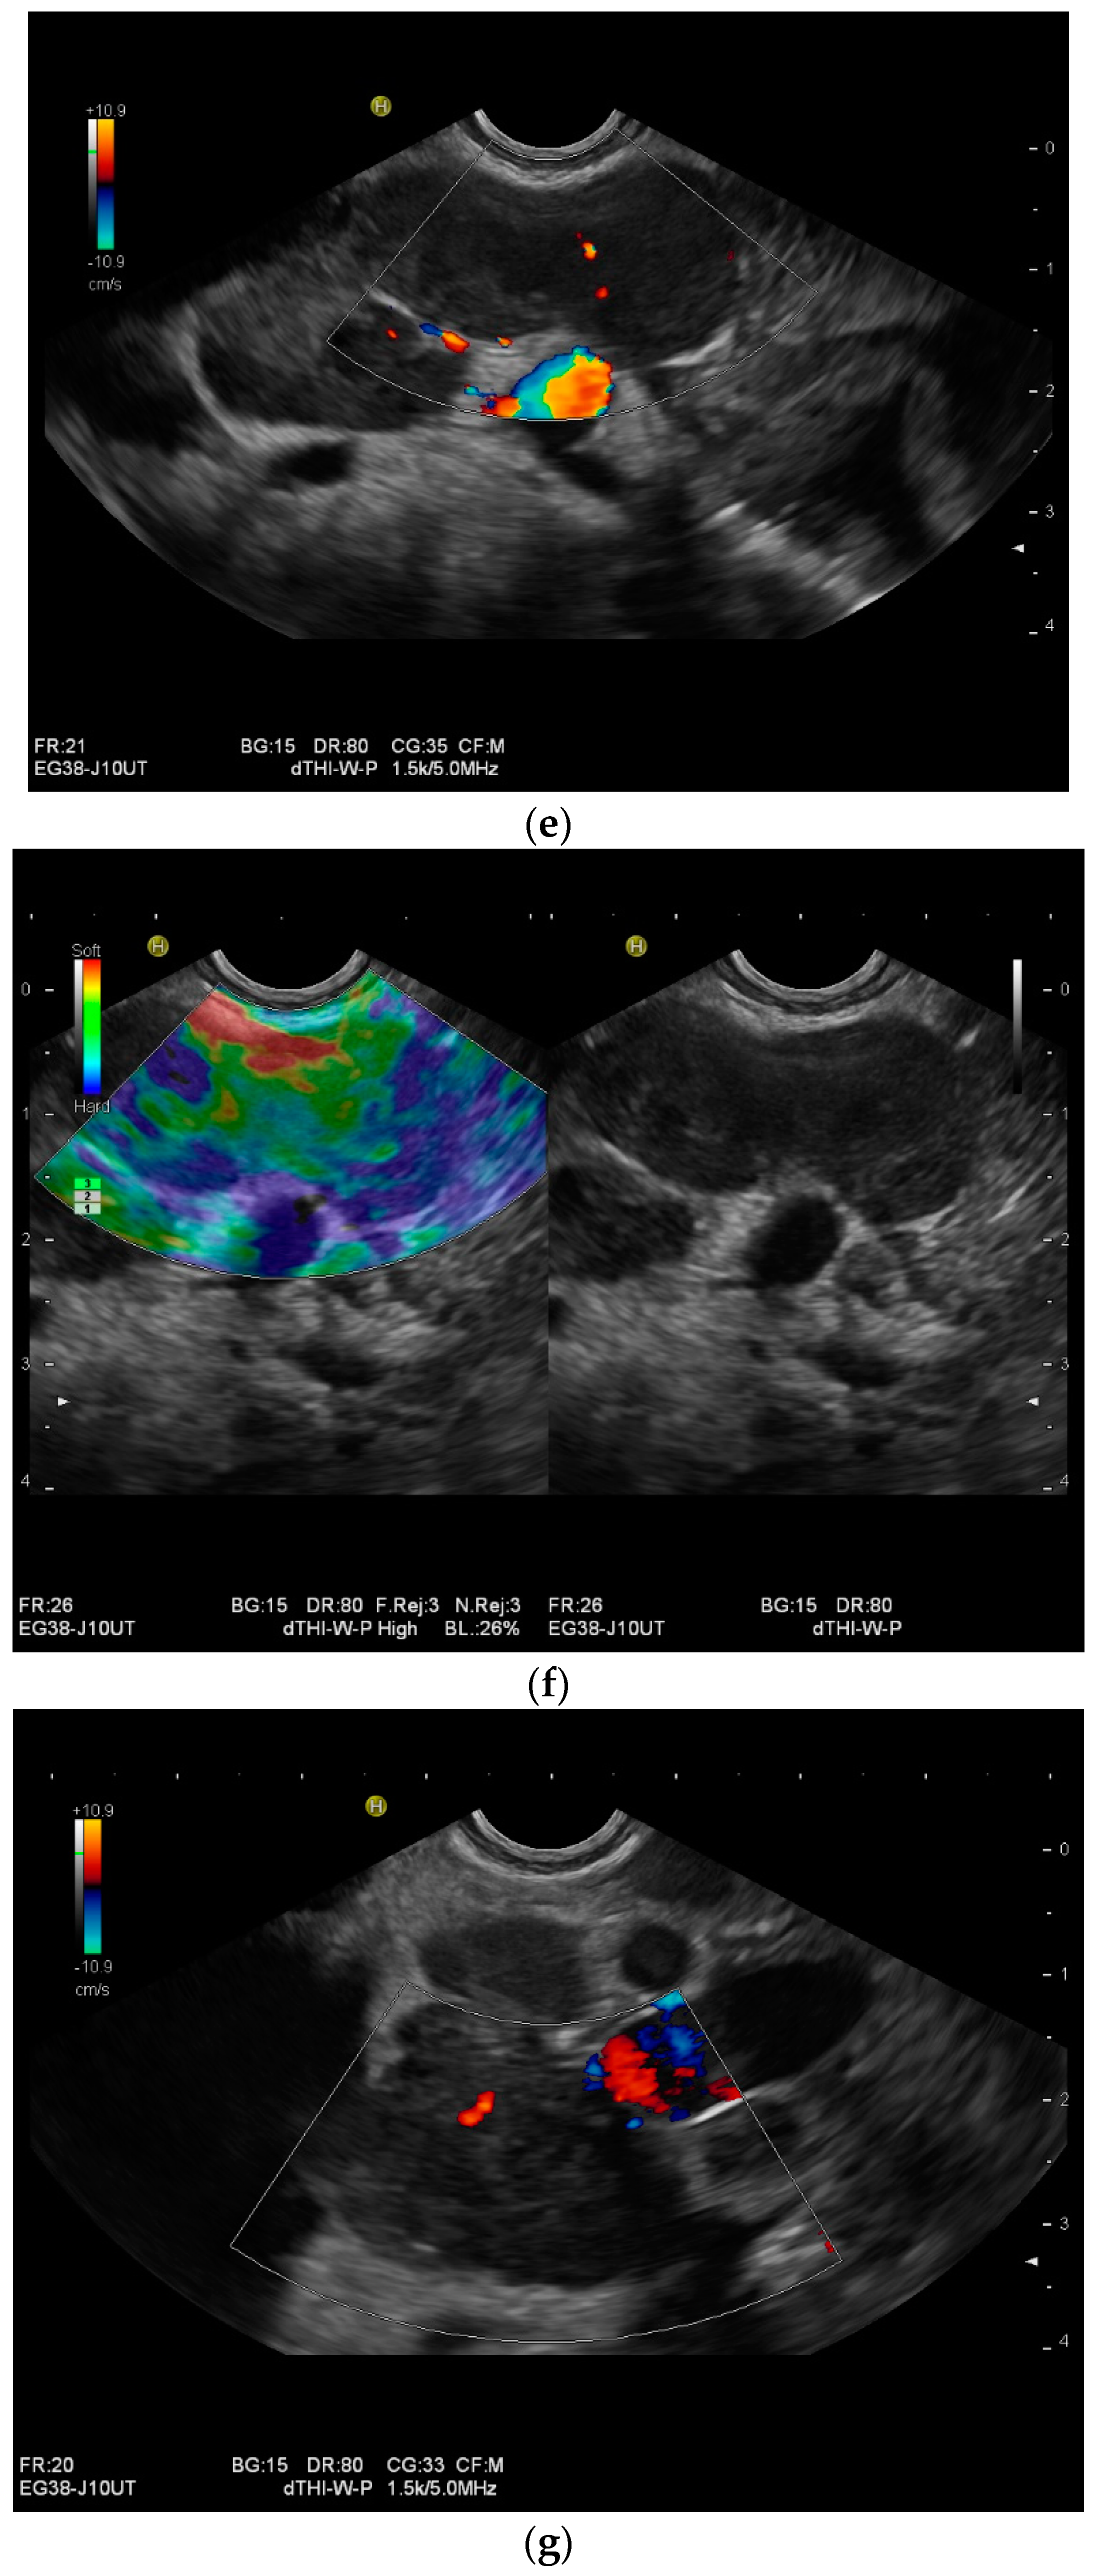

Mediastinal lymph nodes can be biopsied using EUS- or EBUS-guided FNA or FNB. Via paraoesophageal, paragastric, and paraduodenal access, histological specimens can be obtained from further lymph nodes using EUS-guided sampling [41,43,45,46,47,48,49,50] [Figure 2a–m]. The most important differential diagnoses are metastases of malignant tumors, non-Hodgkin’s and Hodgkin’s disease and other infections.

Figure 2.

A case of extrapulmonary tuberculosis: 33 y/o male from a country at high risk of tuberculosis. Thoracic pain and fever led to a suspicion of pericarditis. There was no pericardial effusion. There were no pulmonary infiltrations or pleural effusions in the chest CT, but there were enlarged mediastinal lymph nodes. Ultrasound and CT also showed subdiaphragmal enlarged lymph nodes and small nodular splenic changes. The diagnosis was confirmed using the transgastric EUS-guided biopsy (19 G Olympus) of the lymph nodes in the hepatic hilum. Enlarged lymph nodes in the hepatic hilum (a); adjacent to the pancreatic head (b); transabdominal ultrasound (TUS) using a linear transducer of 9 MHz. The hypoechoic central parts are conspicuous (a,b). Rounded lymph nodes are observed as being peripancreatic (c) and as being in close proximity to the gallbladder wall (d). The lymph nodes are visualized between the markers. In the EUS, paragastric lymph nodes are enlarged, rounded, very hypoechoic, with hypoechoic central parts, and forming conglomerates. A central vascular hilum cannot be delineated in the CDI (e). The hypoechoic central parts are softer during elastography (f). EUS also shows enlarged hypoechoic lymph nodes in the hepatic hilus, with hypoechoic central parts that lack a central vascular hilum (g). Elastographically, the lymph nodes are indifferent (h). The diagnosis is confirmed using EUS-guided biopsy (i) with evidence of granulomatous inflammation, caseous necrosis, detection of acid-fast rods, and Mycobacterium tuberculosis in the PCR. In the spleen, single hypoechoic lesions < 5 mm are visible during transabdominal ultrasound using a linear transducer of 9 MHz. Otherwise, fine-grained hypoechoic lesions can only be guessed at (j). With magnification using a 9 MHz transducer, multiple hypoechoic lesions < 3 mm can be delineated (k). These do not reveal any vessels in the Power Doppler (l). EUS confirms multiple hypoechoic splenic lesions, in line with splenic tuberculosis (m).